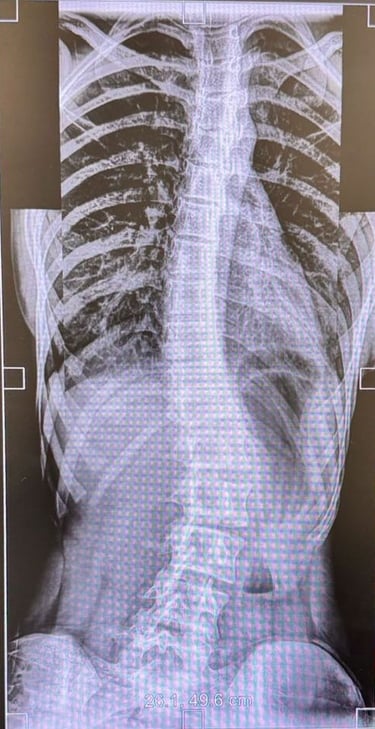

Comprehensive evaluation and surgical correction of scoliosis, kyphosis, and post-infective or traumatic deformities.

Using 3-D planning and intra-operative neuromonitoring, Dr. Sivaraj achieves precise alignment and improved posture while maintaining spinal balance.

Special Expertise:

Adolescent idiopathic scoliosis

Chiari-related and congenital scoliosis

Post-tubercular kyphosis

Scoliosis & Spinal Deformity Correction